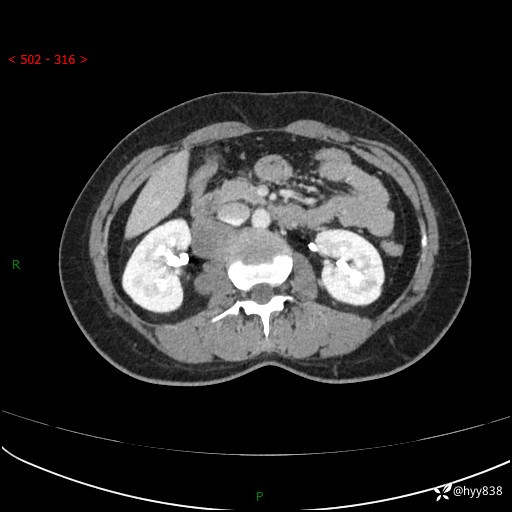

简要病史:患者于1天前因体检发现右旁肾占位,无肉眼血尿,无畏寒发热,无咳嗽咳痰,无腰腹部疼痛不适,无尿频尿急症状,起病来,患者未行特殊治疗,为求进一步诊治,门诊以"右侧腹膜后肿物"收治入院。 发病来患者精神、饮食、睡眠良好,小便如上,大便正常,体重无明显变化。

辅助检查:CT

临床诊断:腹膜后肿物

上腹部CT增强(动脉期+实质期)(外院平扫)